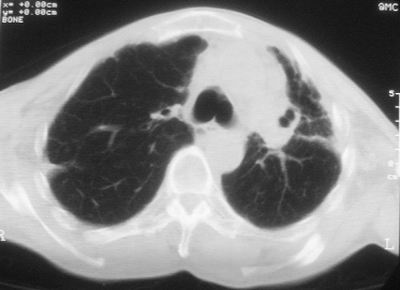

标题: CT11864:男,47岁,反复咳嗽、咯痰、咯血3年,请分析. [打印本页]

患者,男,47岁,反复咳嗽、咯痰、咯血3年,再发5天。痰培养未找到真菌、抗酸杆菌、癌细胞。

左肺上叶体积明显缩小,其内见多发透光区,纵隔向左侧移位,左肺下叶多发班片状病灶,边界模糊,1左肺上叶先天肺发育不全,2左肺下叶肺炎,

左肺上叶结核伴肺纤维化,纵隔移位,左肺下叶感染性病变,建议抗炎抗结核后复查,双肺气肿.

以下是引用xulianj在2008-2-25 21:01:00的发言:[br]左肺上叶结核伴肺纤维化有霉菌球形成,纵隔移位,左肺下叶感染性病变,建议抗炎抗结核后复查,双肺气肿.

考虑:左肺慢纤伴霉菌球形成、双肺全小叶型肺气肿。

1)考虑为:左肺上叶肺结核(空洞形成),伴左下肺感染;不排除霉菌感染可能。2)肺气肿。

左肺上叶结核伴肺纤维化空洞形成并左肺下叶感染,纵隔牵拉移位,建议作进一步检查排除左侧肺霉菌感染可能。